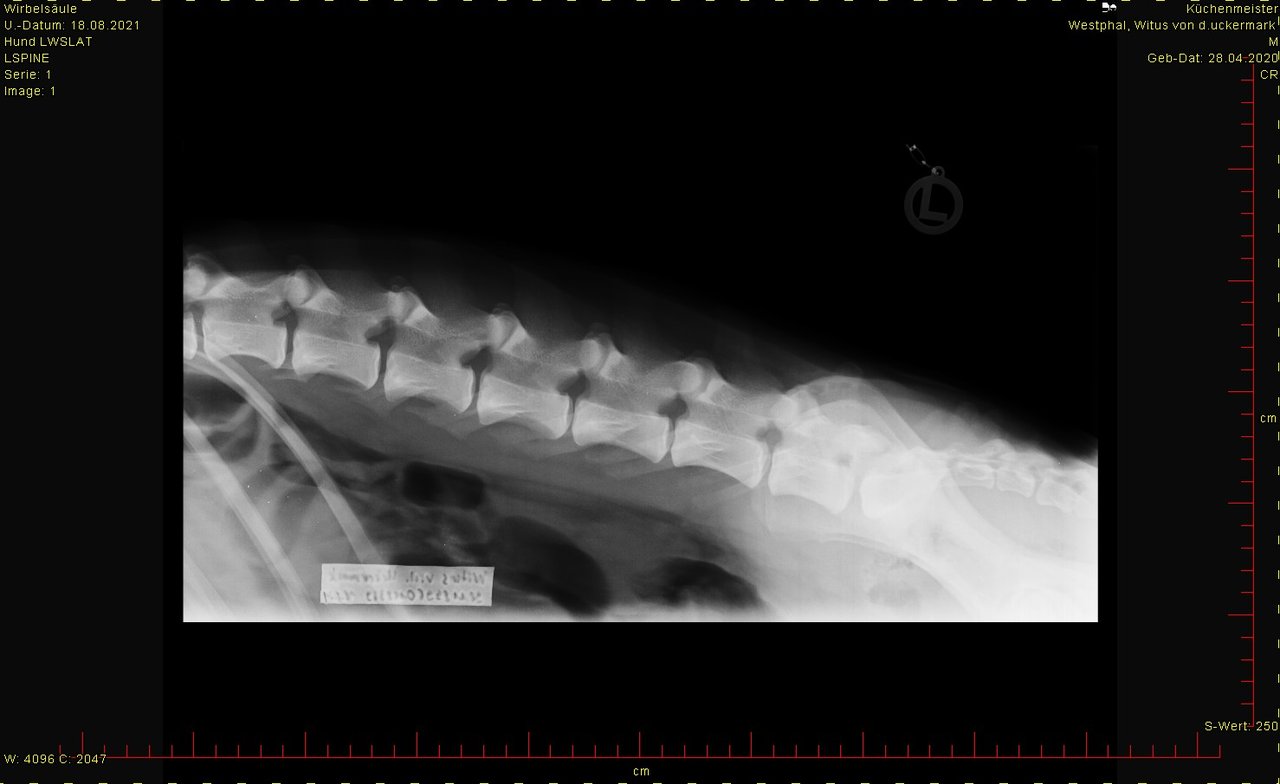

ED hat er nicht, LÜW sah auch ok aus.

hier das Bild von der Hüfte. Ist HD-Aufnahme, kann man groß ansehen.

Was sagt Ihr dazu?

Aber weil Ihr ja die Bilder mal sehen wolltet hätte es ja sein können, das da jemand einen Blick für hat.

Bei den Ellenbogen traue ich mir keine Bewertung zu, finde aber, dass Hüfte und Rücken okay sind